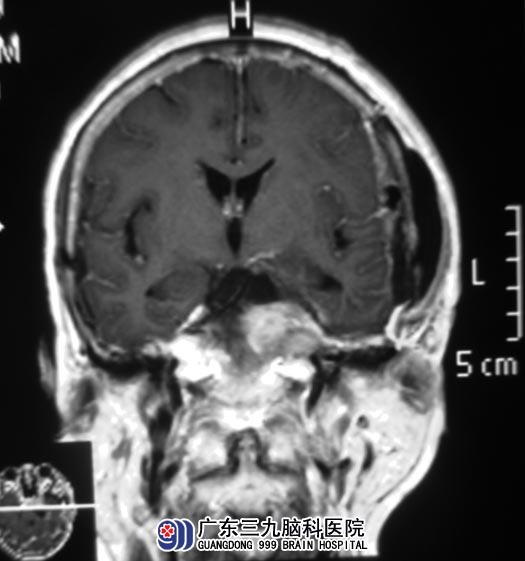

广东三九脑科医院MR检查提示:左侧岩斜区示一不规则形实质性占位性病变,大小约为46.2mm×33.5mm×34.0mm,病变向上生长挤压视交叉,侵犯左侧海绵窦,并突破鞍隔长入鞍内。综合神经外科 鲁明主任初步考虑为脑膜瘤。

完善相关检查后,鲁明主任主刀,在全麻下行左侧岩斜区、海绵窦脑膜瘤切除术,术中沿颅底游离并分离肿瘤,见肿瘤质韧,粉红色,血供丰富,主要位于小脑幕,并长入海绵窦内,包绕左侧颈内动脉及滑车神经,与三叉神经、动眼神经关系密切,在显微镜下将肿瘤顺利切除。术后陆姨未再诉头痛。病理结果为:过渡细胞型脑膜瘤。